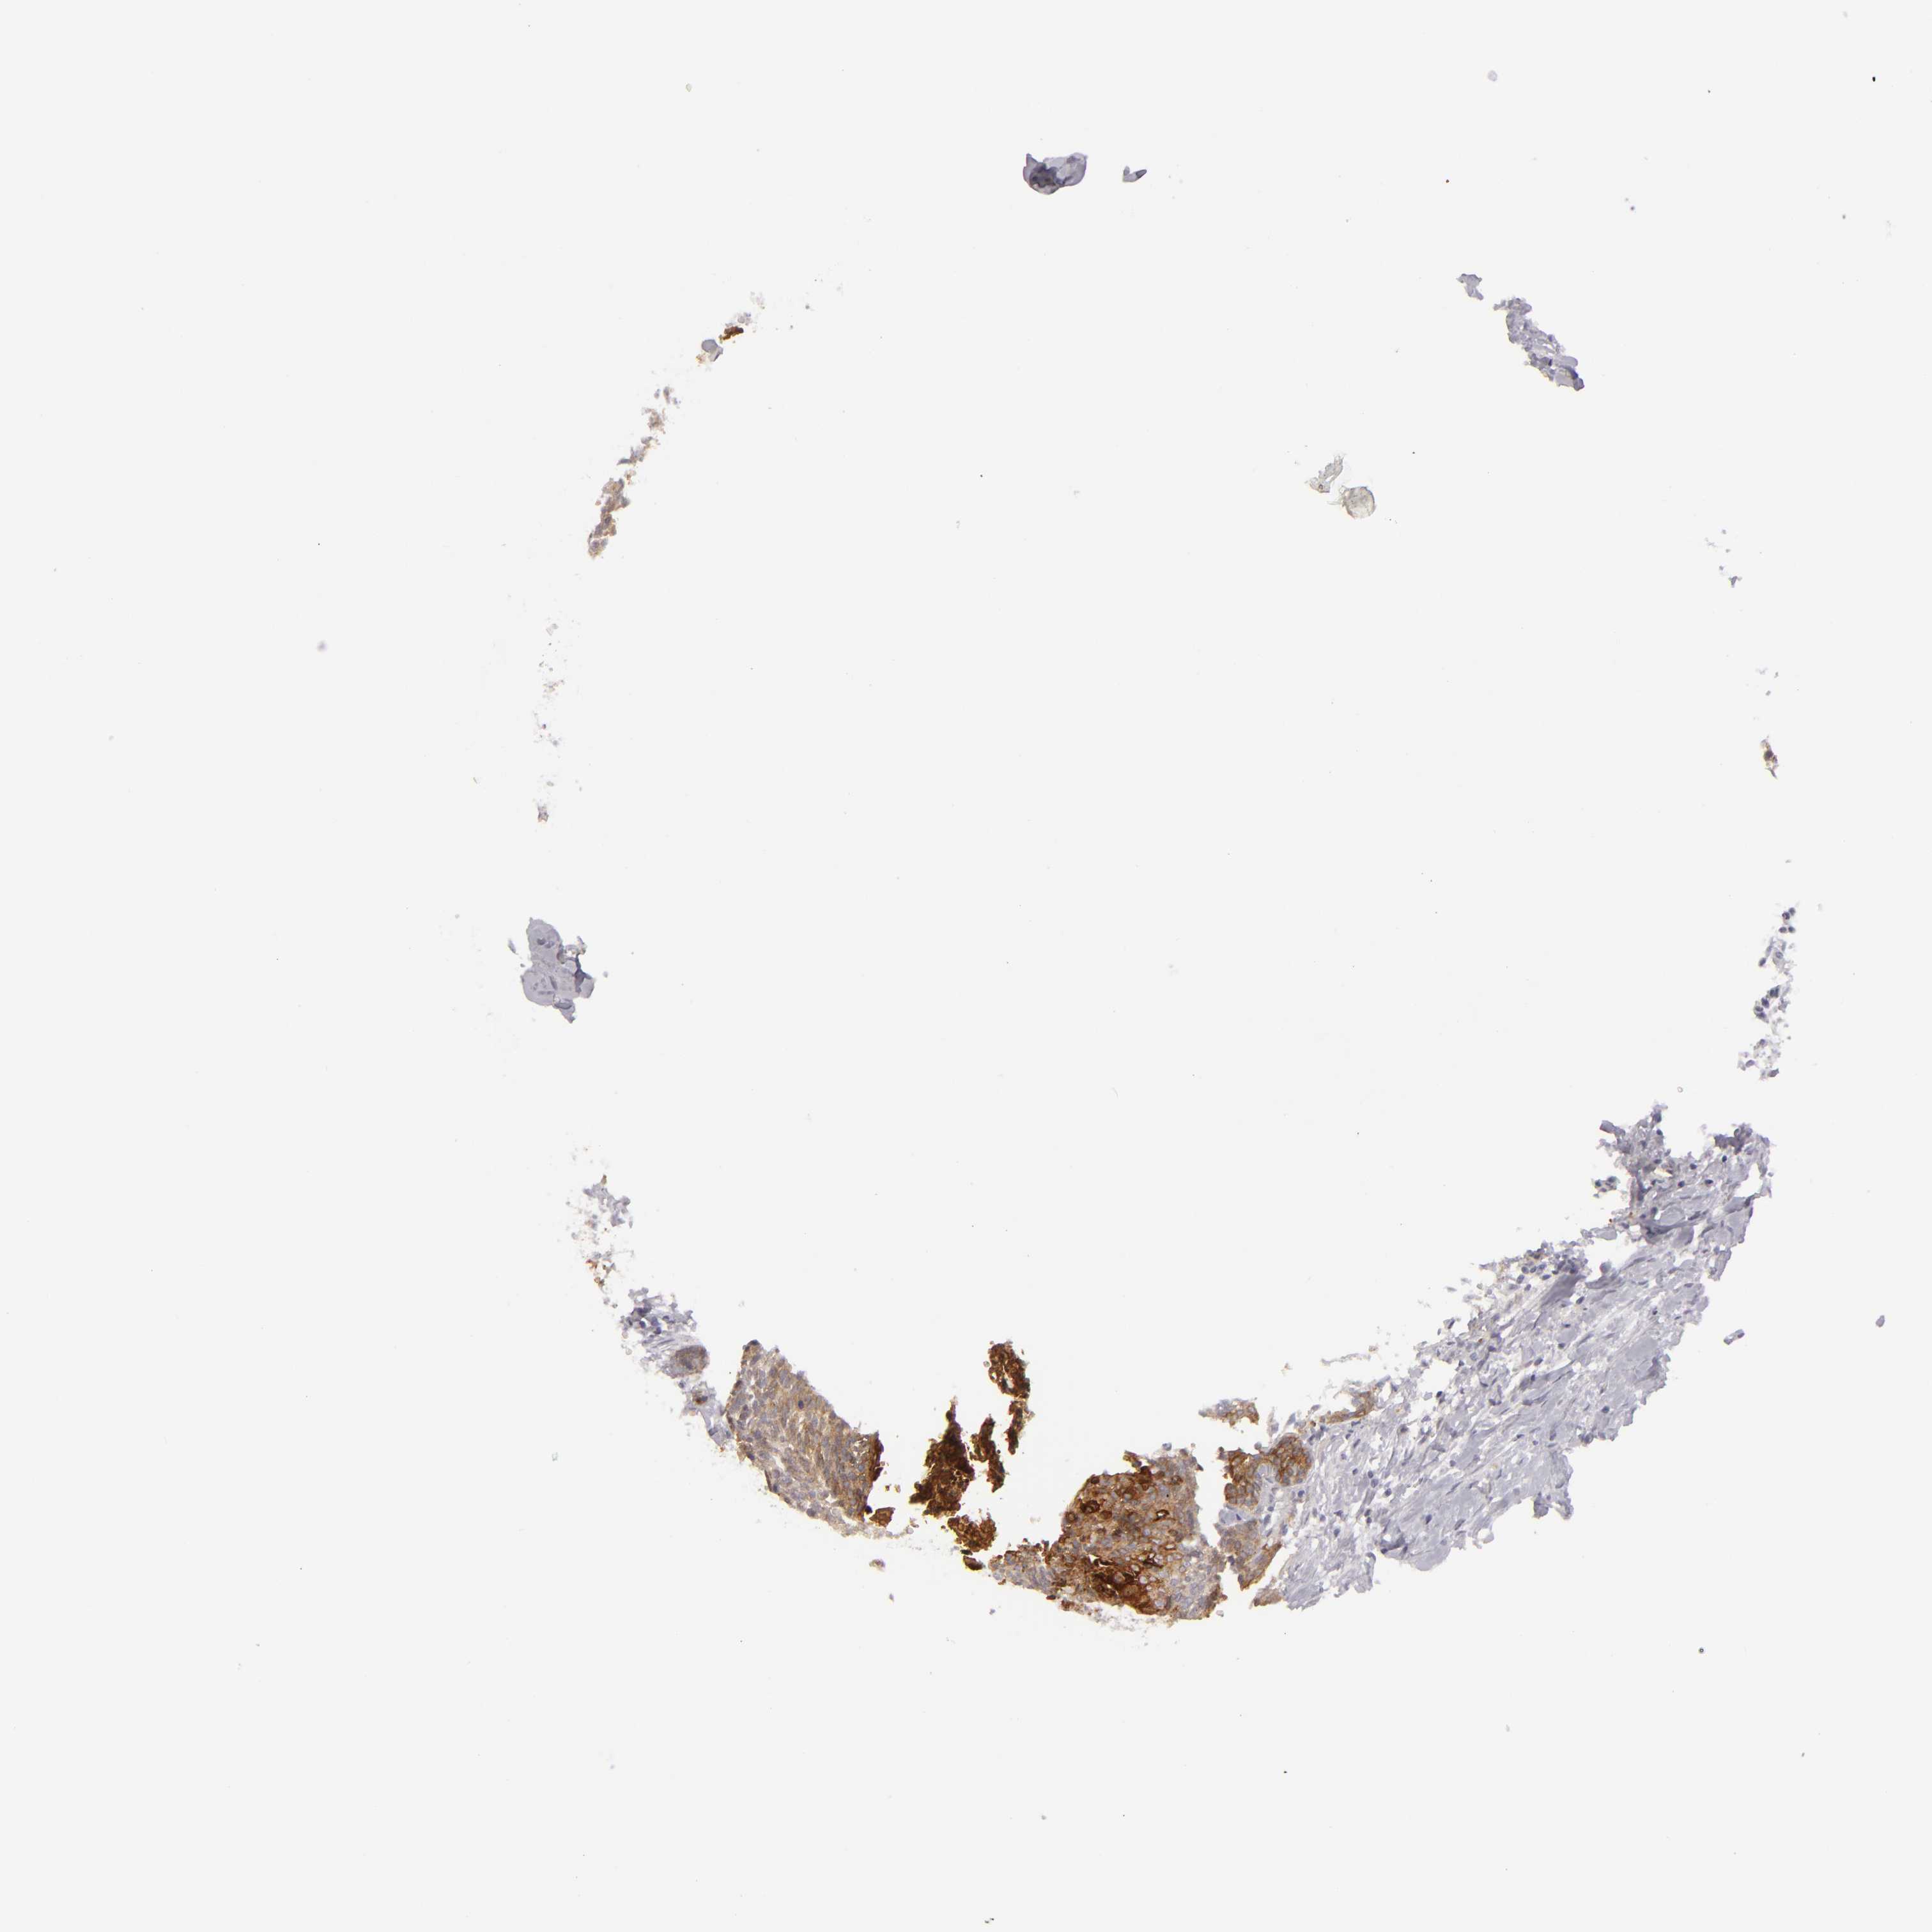

HEAD AND NECK CANCER - Protein expressioni

A mouse-over function shows sample information and annotation data. Click on an image to view it in a full screen mode. Samples can be filtered based on level of antibody staining by selecting one or several of the following categories: high, medium, low and not detected. The assay and annotation is described here.

Antibody stainingi

Antibody staining in the annotated cell types in the current human tissue is reported as not detected, low, medium, or high, based on conventional immunohistochemistry profiling in selected tissues. This score is based on the combination of the staining intensity and fraction of stained cells.

Each image is clickable and will lead to virtual microscopy that enables deeper exploration of all samples and also displays staining intensity scores, fraction scores and subcellular localization as well as patient and tissue information for each sample.

Antibody HPA032047

Antibody CAB002139

Staining

High

Medium

Low

Not detected

Intensity

Strong

Moderate

Weak

Negative

Quantity

>75%

75%-25%

<25%

None

Location

Nuclear

Cytoplasmic/membranous

Cytoplasmic/membranous,nuclear

Squamous cell carcinoma, NOS